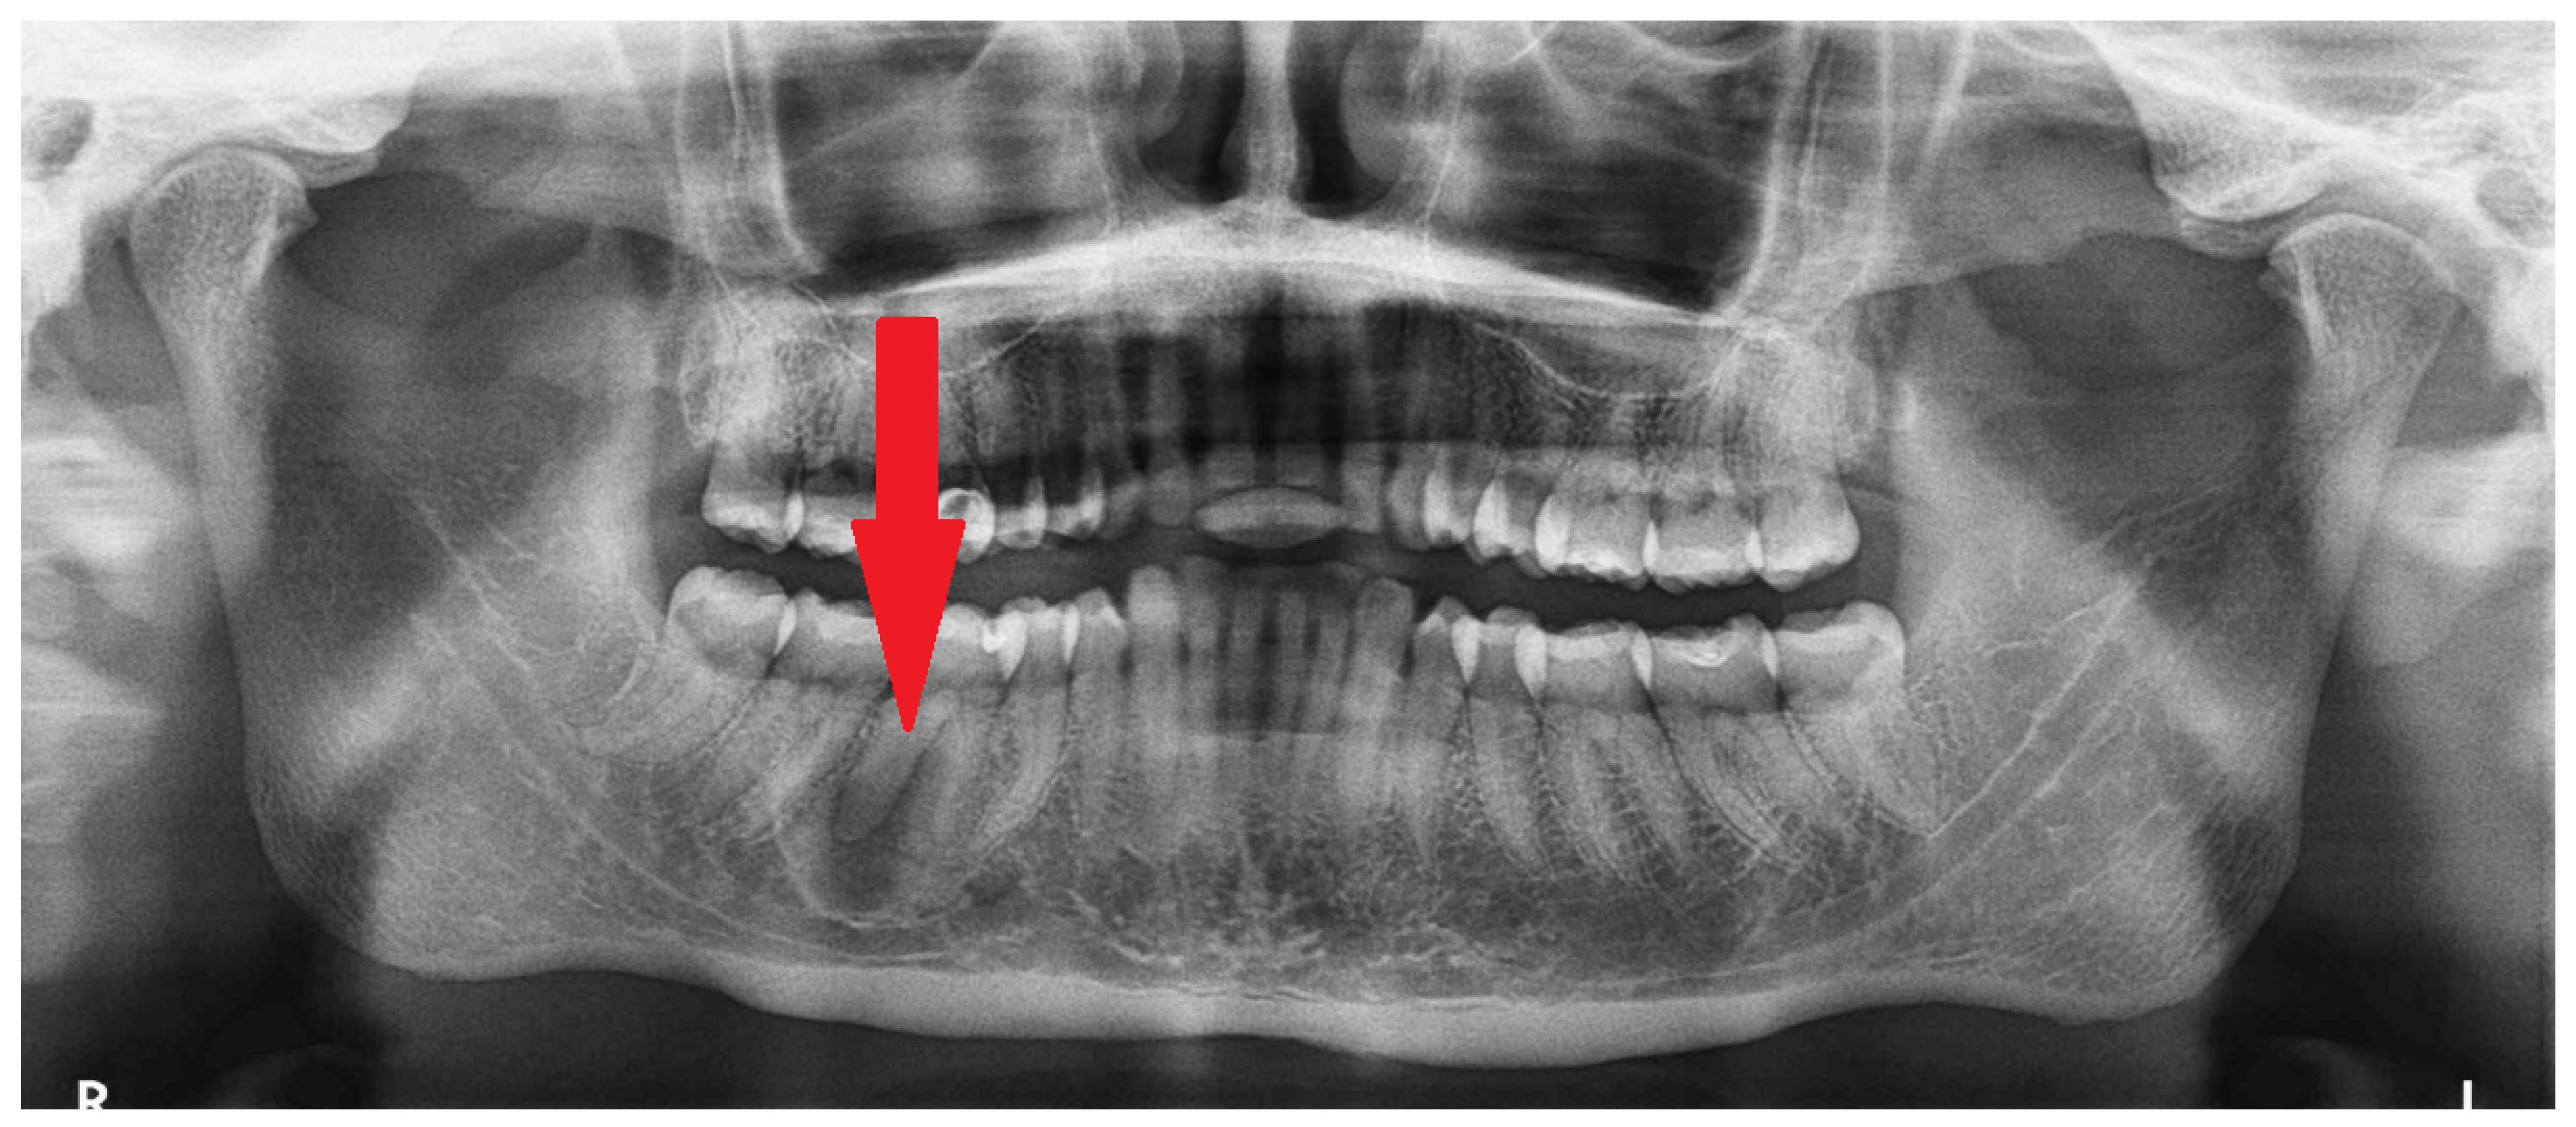

Figure 3. CBCT scans in the coronal and sagittal views—slight bone swelling with cortical thinning (blue arrow) and a non-displaced mandibular canal (yellow arrow). A clear root structure without any erosion, resorptions, or other pathology is visible. The red arrow on the sagittal scan reveals a good condition of the nerve and blood vessels entering the periapical area of the first right molar tooth in the mandible. This cloud-like appearance is characteristic of many lesions in radiologic studies [1,2,3,4,5]. No extracortical bone spread is visible. Identifying the extent of lesion calcification or the occurrences of bone- or tooth-like structures within the cavity could improve diagnostic accuracy. A study conducted by Gennaro et al. confirmed that diagnosis is challenging, but the main goal should always be predicting the right outcome for the patient. Each lesion in the jaw bones requires careful evaluation of the cortical bone, potential calcifications, presence of tooth-like structures, the status of the periosteum, and the formation of any new bones. On the other hand, a study by Merva Soluk-Tekkesin et al. indicated that the most common radiological feature found in their study was a mixed radiolucent/radiopaque internal structure [4]. The cloud-like radiological appearance made it very hard to distinguish between types of bone and fibro-osseous lesions and to determine the most suitable approach. This case underlines how CBCT and biopsy might, in some cases, influence the selection of a proper surgical approach. Many radiological scans of known bone lesions exhibit typical characteristics for each lesion. In this case, radiological differentiation of the lesion was very challenging, especially on PANX and CBCT. This OSF has two different radiological appearances and unclear borders. Quite often, only thorough histopathological evaluation can accurately reveal the different patterns of bone growth, maturation, and calcification that confirm the diagnosis of OsF. Abbreviation—S: surgery side (right).